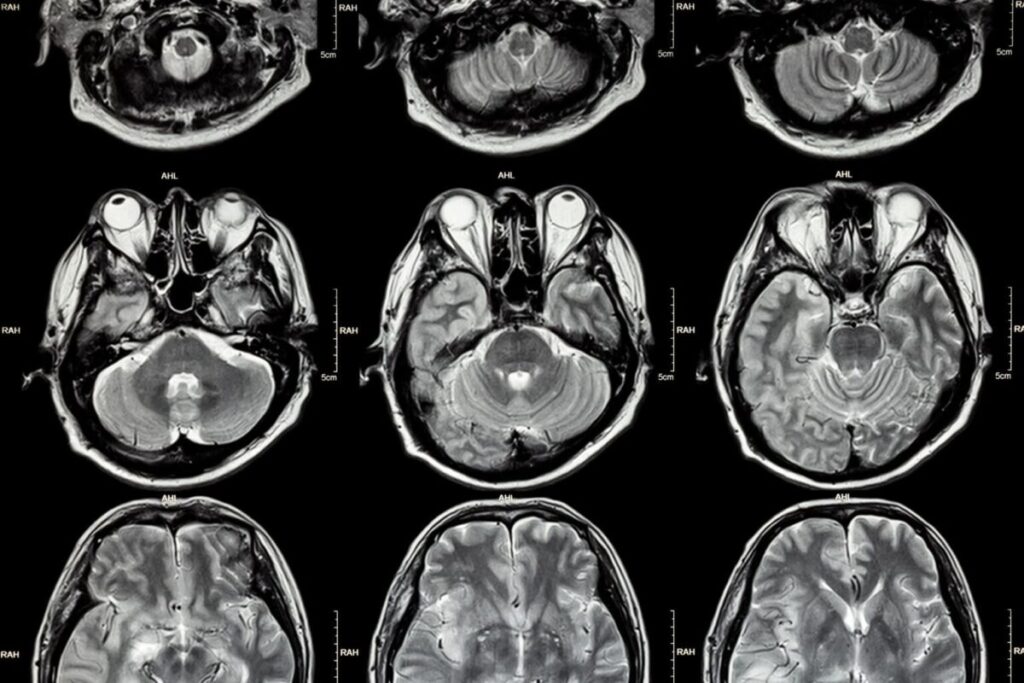

④ MRI(磁気共鳴画像)1970年代後半

原理

磁場と電磁波で水素原子を測定。

特徴

- 高解像度

- 放射線なし

意義

脳構造を詳細に観察可能になった。